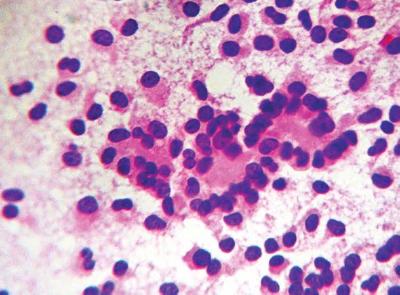

Electrocardiograma: taquicardia sinusal. Radiografía de tórax: Normal. Ultrasonografía abdominal: Hígado normal, vesícula de paredes finas, sin litiasis. Se observa imagen de densidad mixta, bien definida, de cápsula gruesa, de 103 x 94 mm. Tomografía axial computarizada (TAC) de abdomen: Hígado de densidad homogénea. Existe imagen de densidad mixta con cápsula gruesa, de 106 x 92 mm, con zonas hiperdensas en su interior, en proyección de la cabeza pancreática, conducto pancreático dilatado de 6 mm. No se aprecian modificaciones después de la administración de contraste endovenoso. Colangiopancreatografía retrógrada endoscópica (CPRE): No se pudo realizar ante falta de cooperación de la paciente. Biopsia por aspiración con aguja fina (BAAF) guiada por ultrasonografía: Se observa un extendido con marcada celularidad, con células de pequeño a mediano tamaño, poligonales y elongadas, con núcleos ovoides, a veces indentados; nucléolo inconspicuo y citoplasma claro, escaso y eosinófilo. Las células forman un patrón discohesivo, a veces con pequeñas micropapilas o pseudopapilas. Se informa como compatible con una neoplasia epitelial de bajo grado. Se sugiere biopsia.

La paciente fue sometida a cirugía, y se le practicó una pancreatoduodenectomía en la que se encontró una tumoración de 10 x 9 cm, bien delimitada, encapsulada, de consistencia blanda, con superficie abigarrada por la presencia de zonas de hemorragia y necrosis, con áreas quísticas y parches amarillentos. El extendido o raspado citológico transoperatorio y el estudio histopatológico posterior informaron la presencia de una neoplasia epitelial sólida quística del páncreas (figuras 1, 2, 3, 4, 5, 6).

Figura 1. Citología a un lente de menor aumento. Obsérvese un extendido muy celular con células de pequeño a mediano tamaño, con núcleos ovoides, nucléolo inconspicuo y citoplasma ligeramente eosinófilo (H/E 10x).

Figura 2. Extendido citológico anterior a un lente de mayor aumento, mostrando una disposición celular pseudorocetoide o pseudopapilar con escasas mitosis (H/E 40x).

Figura 3. Citología de otros campos del extendido donde se aprecian la formación de papilas y la gran celularidad (H/E 10X).

Figura 4. Microfotografía de una de las áreas de la tumoración. Obsérvese la formación de estructuras pseudopapilares (H/E 20x).

Figura 5. Imagen a gran aumento mostrando las estructuras pseudopapilares con un soporte vascular fino y un tejido conectivo central mixoide (H/E 40x).

Figura 6.Histología a gran aumento de un área sólida. Obsérvese la gran celularidad y las estructuras trabeculadas (H/E 40x)

El estudio citológico mediante punción aspirativa con aguja fina puede ser muy importante, pero sobre todo si se indica al citopatólogo la sospecha de este tumor (11). En nuestro caso no fue así, pues carecíamos de la experiencia en este tipo de tumores. El frotis puede ser altamente celular, con una población monótona de pequeñas células epiteliales que se presentan aisladas o en acúmulos, con pequeñas estructuras papilares; con núcleo redondeado u oval, con caracteres de buena diferenciación y a veces un pequeño nucléolo (2, 6, 11), tal como lo pudimos observar en el estudio practicado a nuestra enferma.